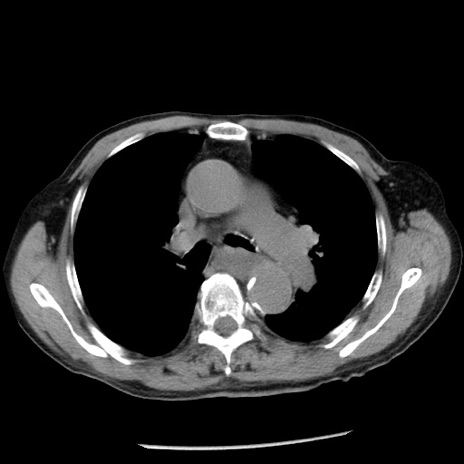

症例26(横断像)

【症例】80歳代男性

【主訴】嘔吐

【現病歴】昨晩2回嘔吐あり、今朝になっても嘔吐あり。来院。

【既往歴】胃潰瘍

【身体所見】意識清明、BT 37.6℃、BP 166/95mmHg、HR 100bpm、SpO2 97%、腹部:平坦・軟、腸蠕動音聴取良好、圧痛なし。

【データ】WBC 21900、CRP 1.46